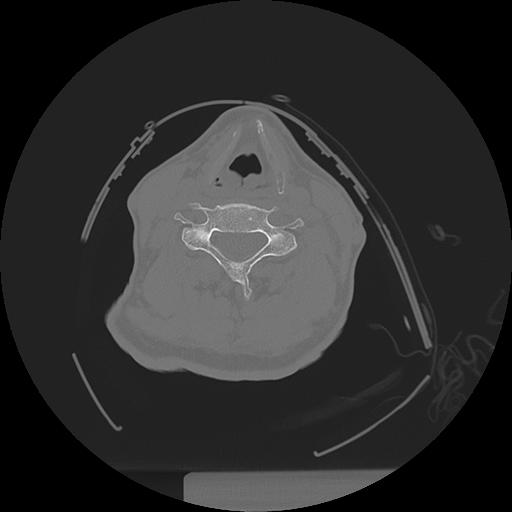

11 HUESO,,Axial,2.0,HUESO,,